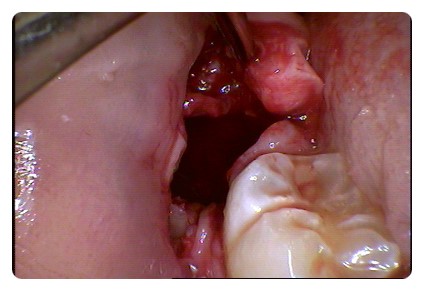

오늘 사랑니 발치 때문에 방문을 하신 환자분인데

사랑니와 신경관이 붙어 있어 상당히 어려운 케이스입니다.

결과적으로 이렇게 깔끔하게 사랑니가 제거가 되었습니다.

이런 잇몸속에 숨어 있는 완전매복 발치는 치아를 통째로 뽑을 수 없기 때문에

조심해서 사랑니를 조각조각 내야 합니다.

사랑니 발치 후 많은 주의사항이 있습니다.

그중에서도 보시는 것처럼 상당히 깊은 곳에서 발치를

했기 때문에 지혈이 잘 되지 않습니다.